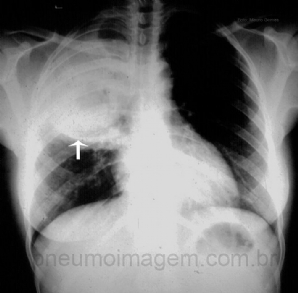

CASO CLÍNICO #19

Paciente com tosse persistente há um mês, febre e sudorese noturnas e perda do apetite. Qual o diagnóstico? Deixe seus comentários abaixo. ***** Patient with persistent cough for a month, fever and night sweats and loss of appetite. What is the diagnosis...